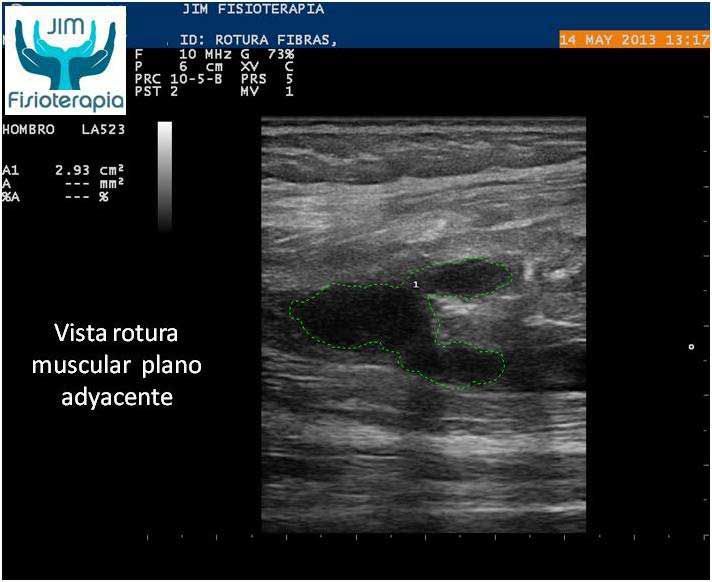

Varón de 47 años, sufre una rotura muscular en el bíceps femoral de la pierna derecha al realizar una brusca contracción excéntrica asociada a movimiento de torsión, al evitar la caída de su motocicleta. Acude a las 72 hrs a nuestra clínica presentando dolor a la palpación, contracción muscular y en la marcha. En la exploración ecográfica se observa una rotura de bordes irregulares.

Se procede a la aplicación de EPI® con el fin de “vaporizar” el derrame producido y favorecer el proceso de regeneración y cicatrización muscular sin fibrosis. En las imágenes se puede apreciar el cambio en el tejido desde la primera sesión, fueron necesarias cuatro sesiones de EPI® hasta lograr la recuperación completa, a partir de la segunda sesión el paciente refirió una desaparición del dolor en la marcha y las actividades cotidianas, complementando su tratamiento con la aplicación de Radiofrecuencia.